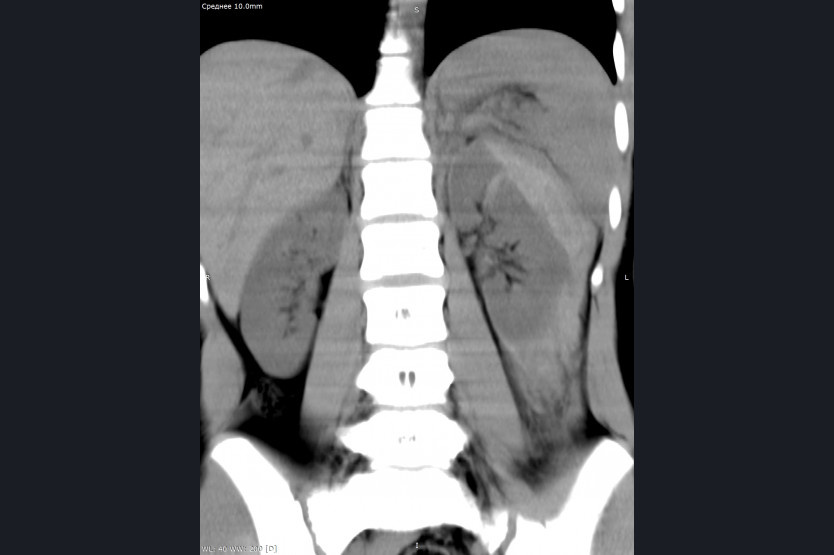

Юная спротсменка во время тренировки 3 февраля ударилась о стойку, на которую была натянута сеть. После чего у нее начались тупые боли в животе, и ее экстренно доставили в хирургическое отделение Детской городской клинической больницы № 1. Там девочку обследовали и провели мультиспиральную компьютерную томографию органов брюшной полости и забрюшинного пространства.

В результате врачи обнаружили разрыв левой почки и кровоизлияние в околопочечную клетчатку с её повреждением. Операционная бригада во главе с детским хирургом провела лапароскопическую операцию, то есть остановила кровотечение, дренировали почку и удалили гематому. Общая кровопотеря при этом составила 250 миллилитров.